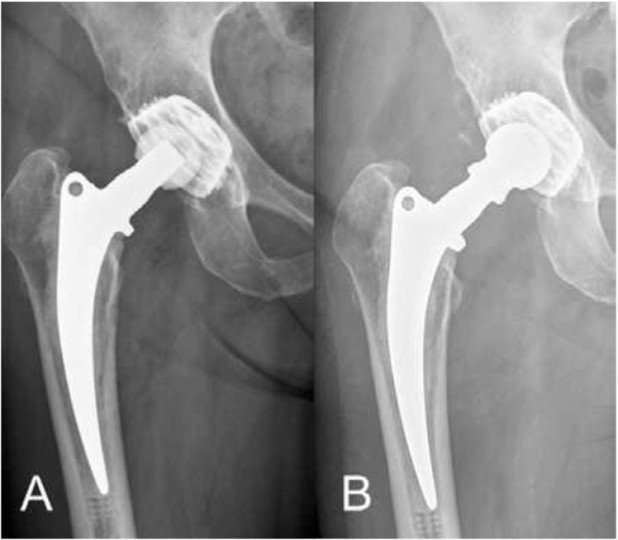

Fall 3

72-jährige Patientin mit zunehmenden chronischen Luxationen des Prothesenkopfs und damit verbundener Stand- und Gangunsicherheit (Abb.6). Zusätzlich haben massive degenerativ und osteoporotisch bedingte Veränderungen der gesamten Wirbelsäule und die dadurch geänderte Beckenausrichtung zu den Luxationen beigetragen. Die noch stabile Verankerung der Hüftprothese an Becken und Femur (Oberschenkelknochen) machte lediglich einen Wechsel der beweglichen Teile (Polyethylen-Inlay und Kopf) nötig. Durch die Verlängerung des Prothesenkopfs wurde die Hüfte wieder stabil, es traten keine weiteren Luxationen auf. Die minimalinvasive Chirurgie ermöglichte, dass die an verschiedenen RA-assoziierten Gelenksveränderungen leidende Patientin schnell und sicher mit Vollbelastung mobilisiert werden konnte.